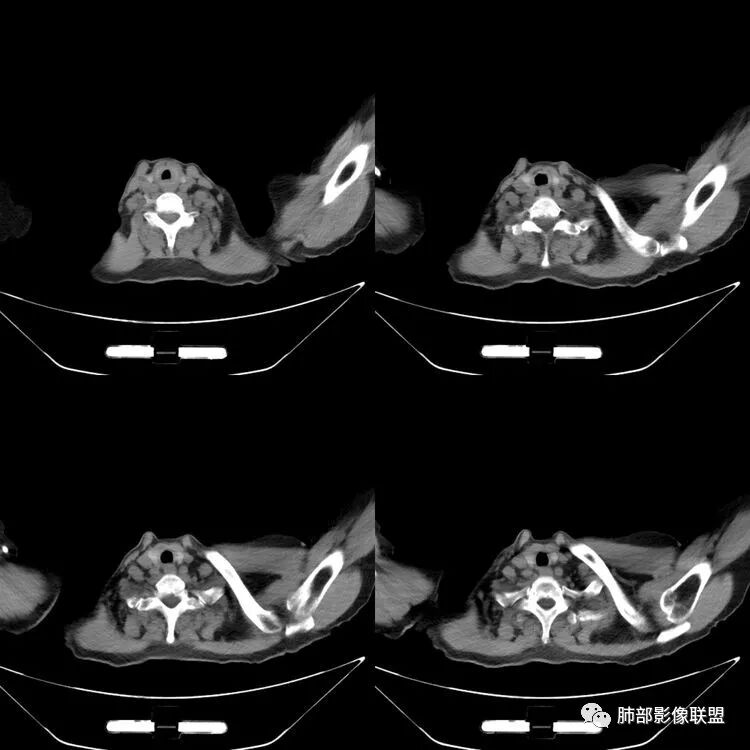

患者,女,64岁,反复咳嗽、咳痰、胸闷10年,加重2周患者10余年来每当受凉感冒出现咳嗽、咳痰、胸闷,有时痰中带血,输液治疗(具体不详)可好转。既往有声带肥厚手术病史。CT示气管、主支气管及分支支气管管壁弥漫性增厚累及膜部,局部伴钙化,管腔狭窄,考虑淀粉样变性

患者,女,64岁,反复咳嗽、咳痰、胸闷10年,加重2周。气管支气管及两肺下叶 支气管弥漫性的环状增厚,管腔扩张,管腔感觉比较松弛。第一感觉,气管支气管淀粉样变。鉴别诊断,1、支气管内膜结核,肺内散在一些支气管的播散病灶,粟粒结节为主,形态比较单一。2、复发性的多软骨炎,就得了解一下其他部位,有没有多个部位的软骨炎。这个病人右侧胸廓缩小,升主动脉明显的扩张,其横径明显的超过了降主动脉。

征象很明确

弥漫支气管壁增厚,膜部受累

声带肥厚——受累

隐约见钙化

南边:肺部有肺气肿支气管腔狭窄淀粉样变性?复发性多软骨炎?血管炎?慢支?结核?曲霉菌?南边:一般还是淀粉样变性与复发性多软骨炎鉴别其次就是支气管骨化症,但是骨化下朝上,且壁结节状钙化明显,本例不太支持。至于结核、曲霉菌?1.结核,一般不会这么广泛,支气管壁狭窄后扩张2.曲霉菌可以这么广泛,但是支气管壁管腔扩张,而且附近脂肪间隙有炎性反应,不太支持;3.血管炎,一般合并肺内有病灶,但是声带受累,放待排;4.软骨炎一般全身受累,例如耳廓等;而且膜部不受累,不太支持;倾向于淀粉样变性;淀粉分很多型,气管支气管是最常见的。尘缘:影像上生理性钙化与支气管骨化无法区别,镜检也不好鉴别,需要依赖活检,看粘膜中是否合并炎性改变(淋巴细胞,组织细胞等炎性细胞侵润)来鉴别Coke with ice:经常看到的这种是老年性肺改变,又称年龄相关肺改变。气管和支气管弥漫性软骨钙化,常见老年女性。尘缘:支气管骨化症很罕见的,所以绝大多数还是生理性钙化。对于老年人,无临床症状的钙化,还是基本上都是生理性钙化,无临床意义。大雄:如果管壁钙化伴明显增厚 影像还是提示一下建议支气管镜稳妥些